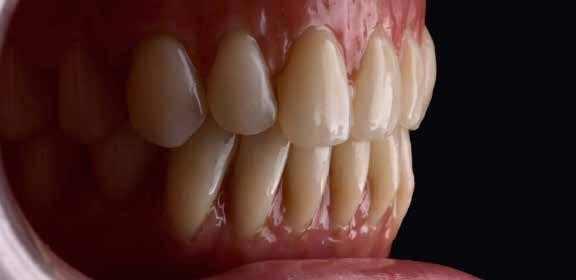

A kívánalmak szerint alul teleszkópos, cirkónium-dioxid stégre támaszkodó PEEK-vázas fogsor, felül teljes kivehető lemezes PMMA-fogsor készült.

a vázakat a Diener Denta Plus plazmakészülék vákuumkamrájába, oxigén-nitrogén gázkeverékbe (49–50. képek) . Ez az eljárás csodálatosan retentív felszínt hoz létre a PEEK-vázon (51–53. képek) . Így előkészítve egyesítjük a blokkban rögzített gyári fogakat Vita VM CC műanyag segítségével a PEEK vázzal (54–58. képek) . A felső fogsor-alaplemezt rózsaszínű PMMA-ból készítettük, majd a két ötös között ezt redukáltuk az egyéniesítéshez (59. kép) . A munkát a Vita Akzent festékekkel és Vita VM LC gingivamasszákkal fejeztük be (60–66. képek) . A segédelemek befogadó helyeit műanyaggal töltöttük fel, amit igény esetén könnyen el lehet majd távolítani, így behelyezhetők lesznek a cirkonoxid-műanyag frikciós segédelemek (67–70. képek) . Végül a teljes szerkezetet a „Highfield-Clean-Prostethics” tisztítási elvének megfelelően (71. kép) plazmával fertőtlenítve csomagoltuk és küldtük a rendelőbe.

Amint megérkezett a végleges pótlás a laboratóriumból a rendelőbe, a stégek felkerültek az implantátumokra (72–73. képek). Ketac Zem-mel ragasztották be őket. Ezt követően kerültek szájba a kivehető fogsorok, még egyszer optikailag ellenőrizve a korrekt illeszkedést. Jó látni, milyen harmonikusan illeszkedik a természetes környezetbe minden. A front optimalizált esztétikája is jól érvényesül (74–81. képek). A tökéletes illeszkedést végül röntgenképpel is ellenőrizték (82.kép).